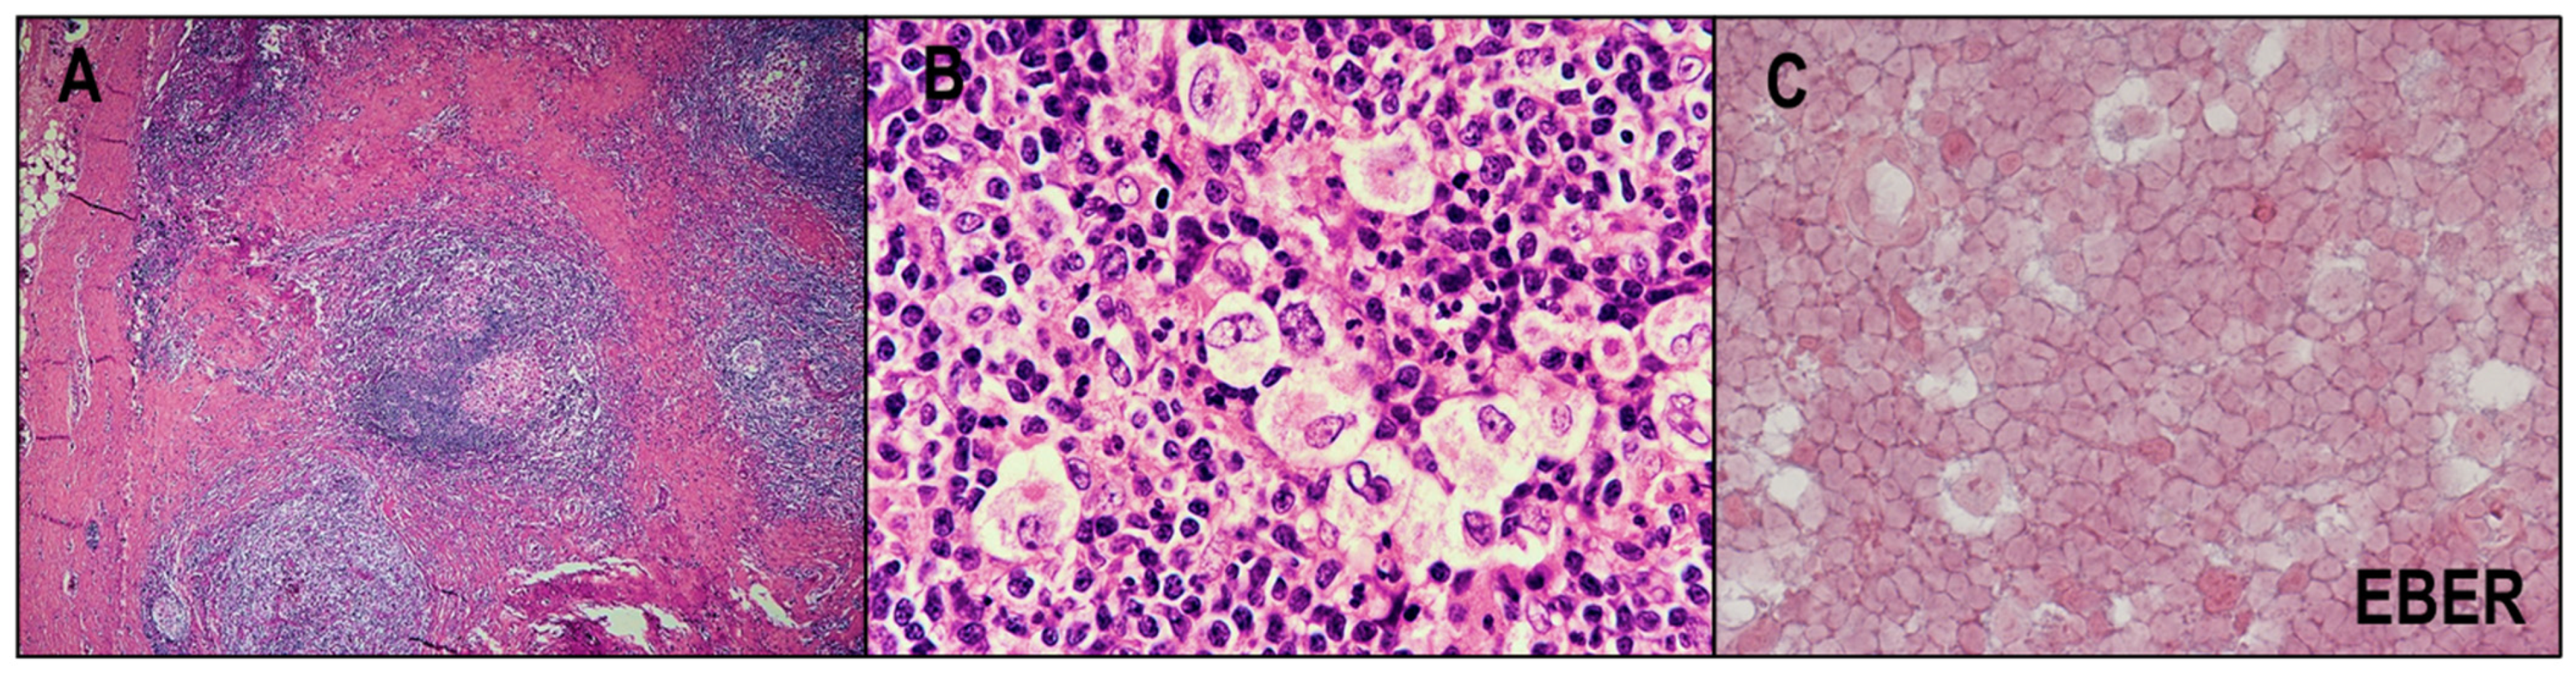

2.1.2. MCCHL

3. NLPHL